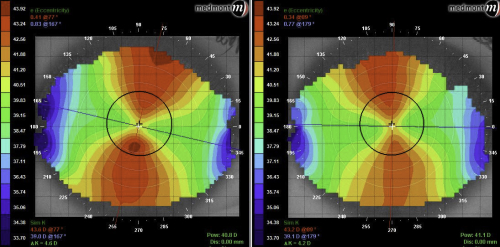

A 67-year-old lady saw me due to the sudden appearance of flashes and floaters the previous weekend. Dilated exam revealed a benign posterior vitreous detachment. The woman had hyperopic LASIK carried out to both eyes 6 years before but she was having more trouble with her distance vision lately. She was also sick of using reading glasses. Unaided distance vision was only R 6/10 and L 6/12 and refraction revealed residual hyperopia of R +0.75/-0.25 x 175 (6/5), L +1.50/-0.50 x 85 (6/5). Her topography confirmed her hyperopic LASIK with tangential maps showing a flatter para-central ring encircling a steeper central cornea. Her left cornea was slightly steeper which was surprising given the higher hyperopic error. Given the foundations were essentially already in place hyperopic post-LASIK orthokeratology was offered to this patient. We chose to further steepen her cornea in a monovision set up, with her dominant right eye for distance and her left for near tasks.

Our patient’s post hyperopic LASIK corneal topography showing the relatively steep central cornea R+L respectively